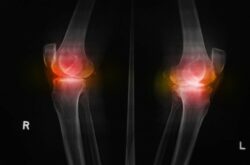

Όπως μας εξηγεί ο Δρ. Βασίλειος Σακελλαρίου, Χειρουργός Ορθοπαιδικός, επικεφαλής του Τμήματος Επανορθωτικής & Ελάχιστα Επεμβατικής Χειρουργικής Ισχίου – Γόνατος της Osteon Orthopedic & Spine Clinic, οι χιαστοί σύνδεσμοι βρίσκονται στο εσωτερικό της άρθρωσης του γόνατος και διασταυρώνονται μεταξύ τους, σχηματίζοντας ένα Χ. Ο ρόλος τους είναι η σταθεροποίηση της άρθρωσης, ο έλεγχος της πρόσθιας/οπίσθιας κίνησης και ενός μέρους της στροφικής κίνησης. Ο πρόσθιος χιαστός είναι ο βασικότερος στροφικός σταθεροποιητής του γόνατος και είναι ιδιαίτερα ευάλωτος σε τραυματισμούς. Οι συχνότεροι παράγοντες που μπορούν να οδηγήσουν σε αυτούς είναι περιβαλλοντικοί, ανατομικοί και ορμονολογικοί. Επίσης, κάποιο ρόλο φαίνεται να παίζουν ακόμη και οι διατροφικές συνήθειες, ο ύπνος και το στρες. Όσον αφορά δε ειδικά στους αθλητές, στον τραυματισμό του πρόσθιου χιαστού συνδέσμου μπορεί να οδηγήσει η ανεπαρκής προθέρμανση, η κακή αποκατάσταση παλαιότερων τραυματισμών, η μυϊκή ανισορροπία εκτεινόντων και καμπτήρων μυών πέριξ του γόνατος, αλλά και η υπερβολική προπόνηση. Η αρχική ένδειξη σοβαρού τραυματισμού του είναι ο χαρακτηριστικός θόρυβος που γίνεται αντιληπτός κατά τη ρήξη του, ο οποίος συνδυάζεται με πόνο, οίδημα και δυσκολία φόρτισης του τραυματισμένου ποδιού.

Θέλοντας να εμβαθύνουν περισσότερο στις αιτίες που οδηγούν σε τραυματισμό των πρόσθιων χιαστών και να ερευνήσουν εάν η κόπωση αποτελεί άλλον έναν παράγοντα κινδύνου, επιστήμονες μελέτησαν αθλητές του στίβου, του μπάσκετ, του βόλεϊ και του ποδοσφαίρου, μέσης ηλικίας 15,4 ετών. Από τα ευρήματα, τα οποία παρουσιάστηκαν στο συνέδριο της Αμερικανικής Ορθοπαιδικής Εταιρείας για την Αθλητιατρική (American Orthopaedic Society for Sports Medicine), διαπιστώθηκε ότι το 44,7% των συμμετεχόντων στη μελέτη διέτρεχε αυξημένο κίνδυνο τραυματισμού μετά από αερόβιες δραστηριότητες υψηλής έντασης. Επιπλέον, το 68% των ατόμων που μελετήθηκαν θεωρήθηκε ότι είχαν μέτριο ή υψηλό κίνδυνο τραυματισμού μετά από αερόβια δραστηριότητα. Ο κίνδυνος τραυματισμού συνδέθηκε με το επίπεδο της κόπωσης, με το φύλο αλλά και την ηλικία, καθώς διαπιστώθηκε ότι αφενός οι αθλήτριες ανεξαρτήτου ηλικίας και αφετέρου οι αθλητές/τριες άνω των 15 ετών είχαν τις περισσότερες πιθανότητες να τραυματιστούν.